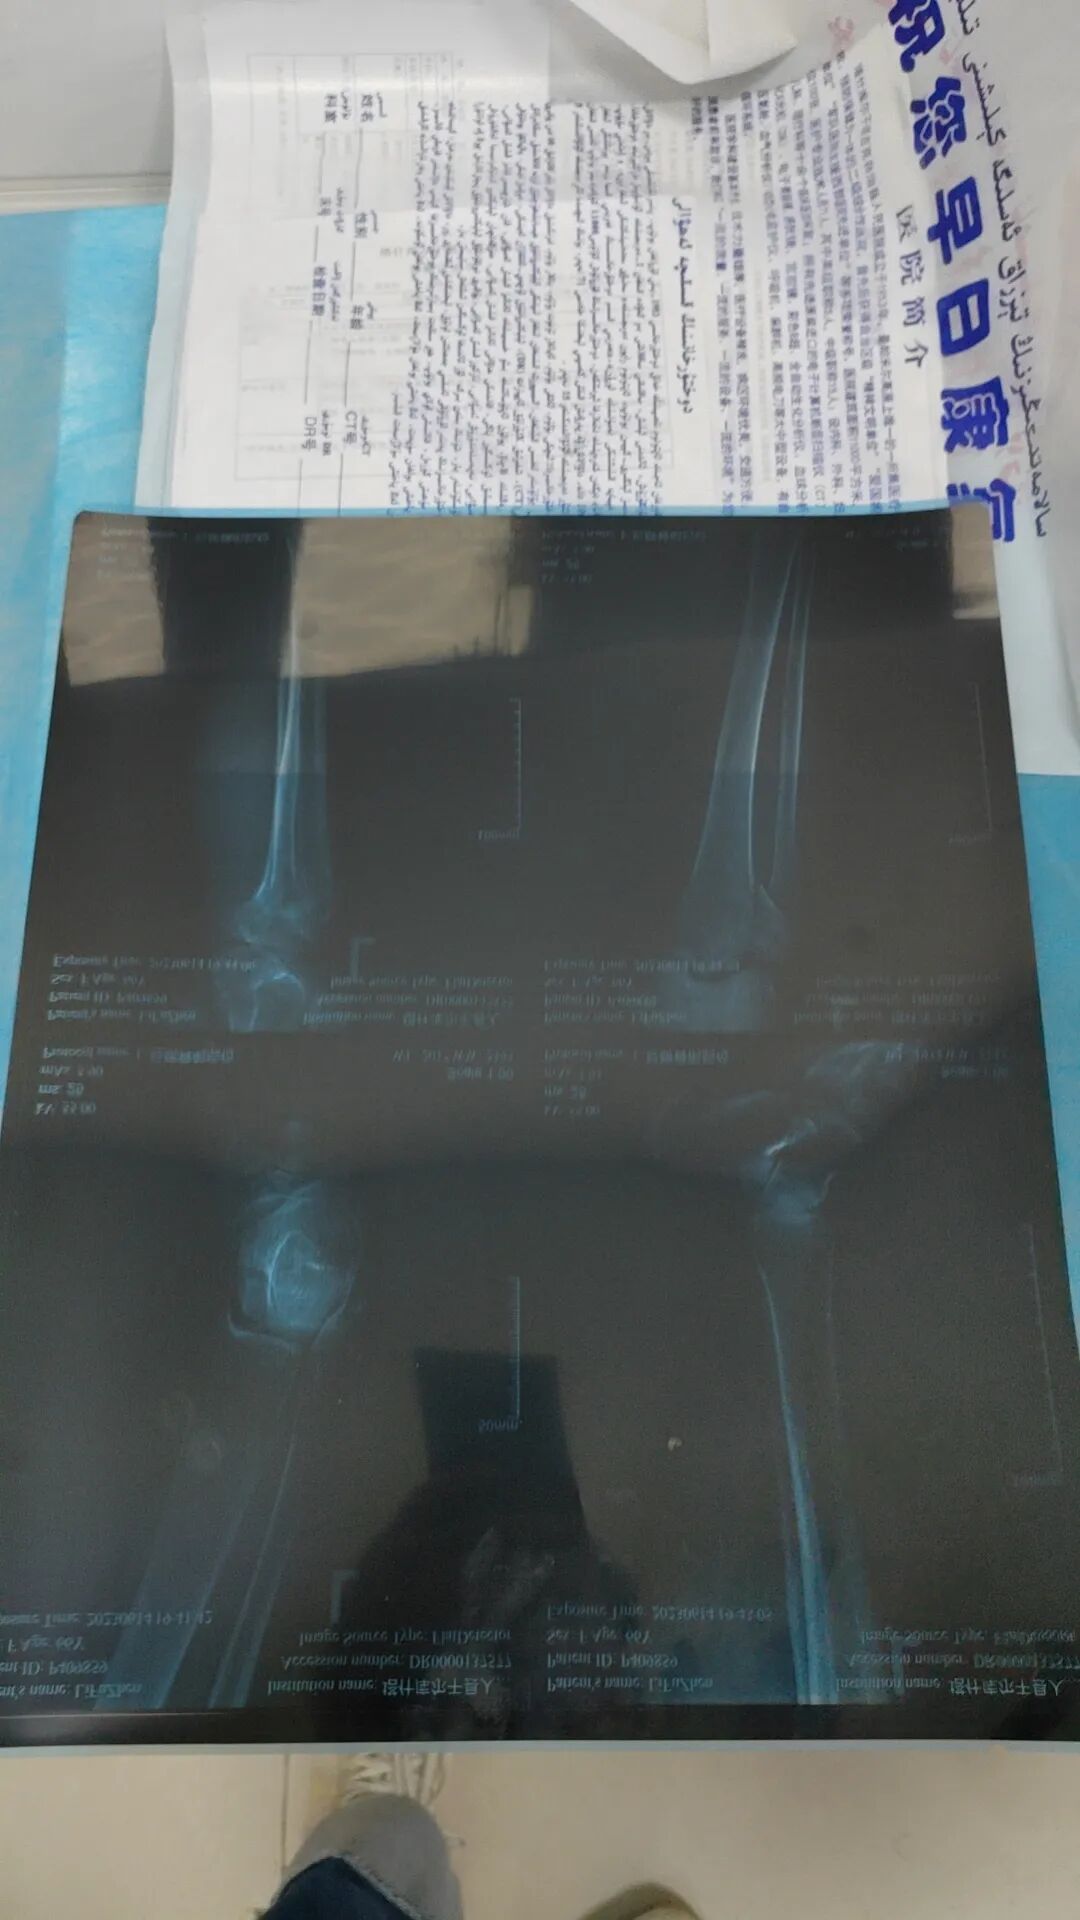

经过医疗报告评估,诊断明确:左侧腓骨头骨折,左侧胫腓骨软组织损伤。客户生命体征平稳,现阶段适合转运。PROMA医疗小组再次与客户本人通话,解释病情情况及权益内容,考虑到转运路途遥远,途中存在医疗风险等不确定性因素,建议客户在当地治疗,待病情稳定后再返回居住地。客户与家人沟通后仍坚持直接返回居住地治疗,为提升客户体验,彰显保司关怀,经我司内部讨论,尊重客户意愿制定返回北京居住地的转运方案。

23:32,PROMA医疗小组结合医疗报告,评估客户病情,并紧急制定了相应送返方案(民航商务舱+救护车+转运医生陪同)。